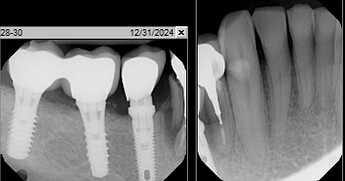

Patient has premolar (#28) with vertical root fracture, radiolucency surrounding the root , and 10mm pocket on lingual. Would you graft this case at time of extraction? or wait and graft later? what time frame and grafting protocol would you utilize?

i would graft at time of extraction. allo/xeno/collagen or PTFE membrane, no tension primary closure w/ PTFE sutures. looks like the site is missing buccal/lingual walls. wait 6-9 months for bone consolidation. Most likely u didn’t place/restore implant #29. so finding parts would be a challenge. sometimes i don’t want to deal with implants i didn’t place. I understand. easier just to focus on the problem tooth #28. instead of opening a pandora box. And if you did make a cantilever 28-29, and the implant #29 fracture. then you would be in a worse situation. then hindsight is 20/20. So from that aspect. i would just focus on #28. instead of doing a cantilever crown to cover #28.